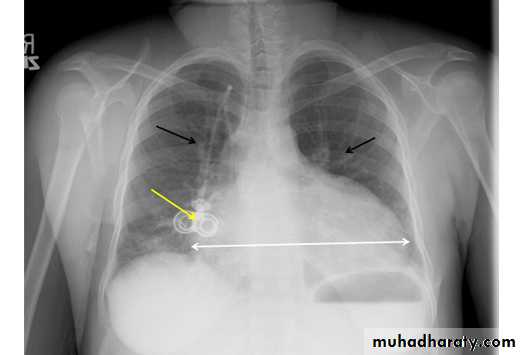

Tension pneumothorax

56.tension pneumothorax left sided aspect

57. tension pneumothorax right sided aspect